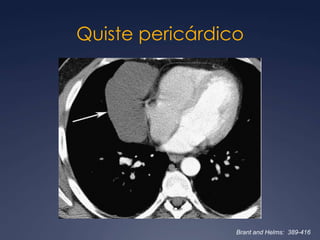

Quiste pericárdicoBrant and Helms:  389-416